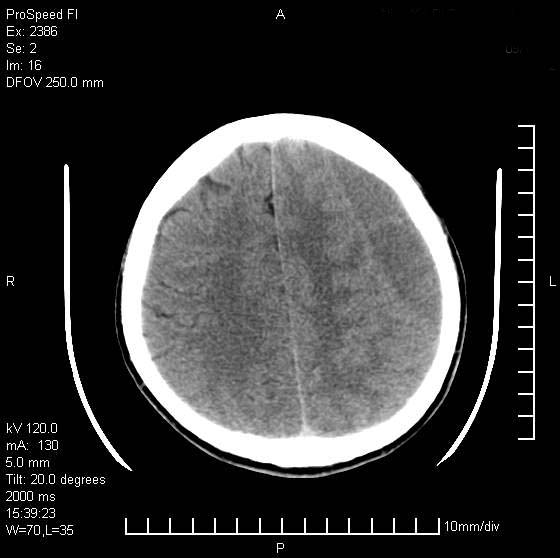

以下是引用天南地北在2007-9-19 18:43:00的发言:[br]典型慢性硬膜外血肿[br][br][本贴已被 天南地北 于 2007-9-19 18:44:11 修改过]

以下是引用曼一拍在2007-9-20 11:06:00的发言:[br]支持慢性硬膜下血肿.[br]慢性硬膜下积液:血肿有包膜,ct值稍高于脑脊液,增强可有染色。不典型者血肿可多呈梭形.是硬脑膜与蛛网膜之间的潜在腔隙内的血肿。[br]鉴别:[br]1\\硬膜外血肿:是颅脑外伤后脑膜或板障内血管破裂,血液在颅骨与硬膜之间积聚所致.通常是脑膜动脉破裂,也可因静脉窦破裂或颅骨的板障静脉出血,发生于外伤的着力部,常与颅骨骨折并存。脑膜动脉出血则急,若是板障静脉出血在则可有慢性。[br]2\\硬膜下积液:(硬膜下水瘤)[br]是由于蛛网膜破裂,脑脊液经蛛网膜破口进入硬膜下腔不能回流。或水肿阻塞而形成。[br]ct表现:颅骨内板下方新月形低密度区近似脑脊液密度;占位效应清,周围无脑水肿。[br]